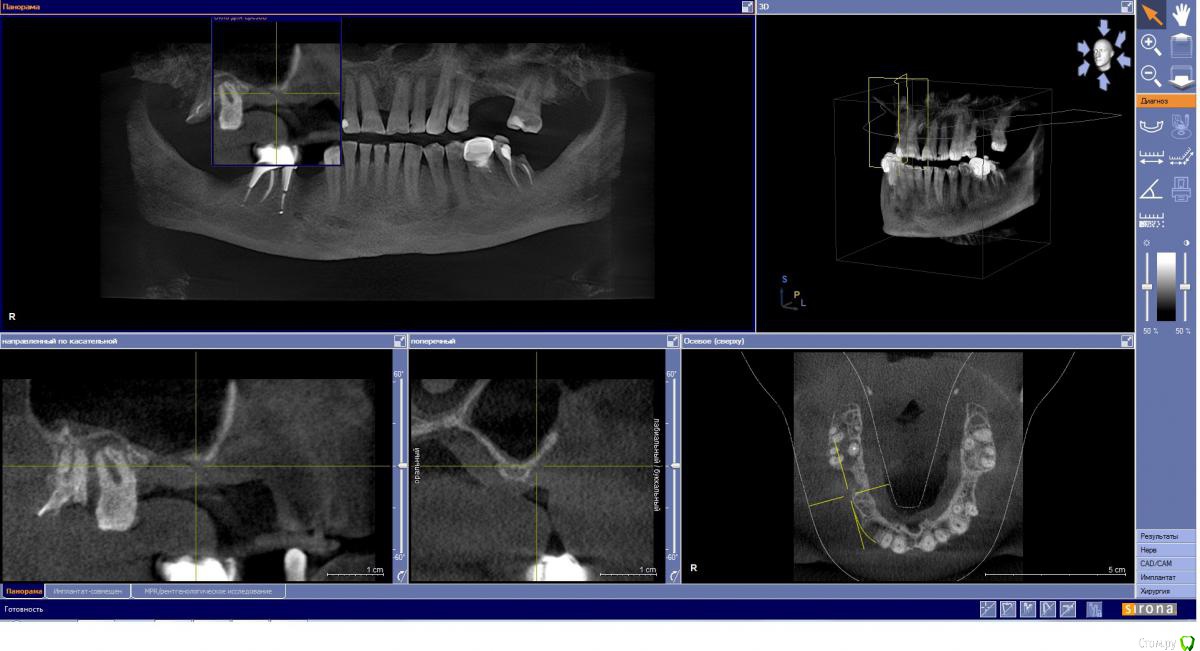

kamranchick Опубликовано 4 мая, 2018 Поделиться Опубликовано 4 мая, 2018 Обратился пациент после очередной халтуры которыми радуют меня коллеги из соседних клиник)фотопротокол ни как у Сашки Гудкова но более-менее понятно))Обратился пациент, в соседней клинике удаляли зуб, корень протолкнули в пазуху, далее пациент попал в ЧЛХ, там сделали радикальную гайморотомию, все достали, и вот попал пациент ко мне, так как в другой клинике сказали что у вас тут залу*а, а не кость, ну и погнали.1. пытался остро отслоиться, перфа на перфе, закрывал prf, мембранами, губками, стики бон + синус имплантация. ожидание 9 месяцев2. Пластика мягких тканей ожидание 2 месяца. 13 Ссылка на комментарий

kamranchick Опубликовано 4 мая, 2018 Автор Поделиться Опубликовано 4 мая, 2018 а рентген?))Есть кт до, и есть панорамник)завтра могу это все скинуть если интересно Ссылка на комментарий

Kazankov.Egor Опубликовано 5 мая, 2018 Поделиться Опубликовано 5 мая, 2018 Обратился пациент после очередной халтуры которыми радуют меня коллеги из соседних клиник)фотопротокол ни как у Сашки Гудкова но более-менее понятно))Обратился пациент, в соседней клинике удаляли зуб, корень протолкнули в пазуху, далее пациент попал в ЧЛХ, там сделали радикальную гайморотомию, все достали, и вот попал пациент ко мне, так как в другой клинике сказали что у вас тут залу*а, а не кость, ну и погнали.1. пытался остро отслоиться, перфа на перфе, закрывал prf, мембранами, губками, стики бон + синус имплантация. ожидание 9 месяцев2. Пластика мягких тканей ожидание 2 месяца.К кому сходить на мягкие ткани? Посоветуйте пожалуйста. Ссылка на комментарий

Eddie Опубликовано 7 мая, 2018 Поделиться Опубликовано 7 мая, 2018 У вас тут в области 13 и 15 диаметры имплантатов 3.5(3.8)? Выдержат такую конструкцию? Ссылка на комментарий

kamranchick Опубликовано 7 мая, 2018 Автор Поделиться Опубликовано 7 мая, 2018 У вас тут в области 13 и 15 диаметры имплантатов 3.5(3.8)? Выдержат такую конструкцию?ну да, а что ей будет) связанная конструкция, на израиле 3.75, служат) Ссылка на комментарий